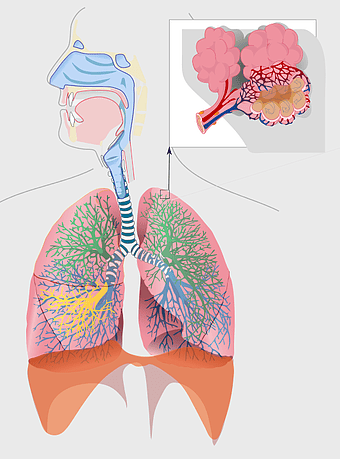

lungs illustration, respiratory system diagram, human lungs anatomy, pulmonary alveolus structure, bronchial tree visualization, trachea and bronchi, lung lobes detail -